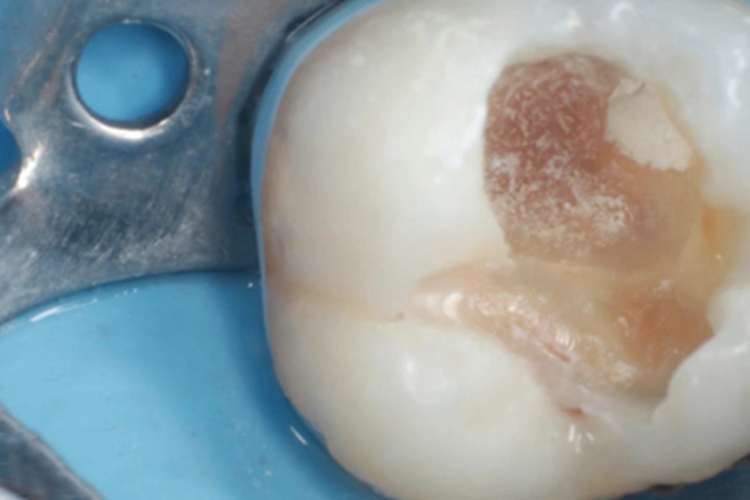

年轻恒牙龋早期可表现为白斑和黑斑,不及时治疗,随着疾病进展,可表现为牙齿大块发黑,在去除后可腐坏发黑的牙体组织后可出现很深的龋洞,可以露出血液及淋巴液等物质组成的渗液。

年轻恒牙龋可由医生进行充填治疗,对于早期的年轻恒磨牙,提倡采用微创的预防性树脂充填术、改良的预防性树脂充填术;深龋必要时考虑二次去腐修复。